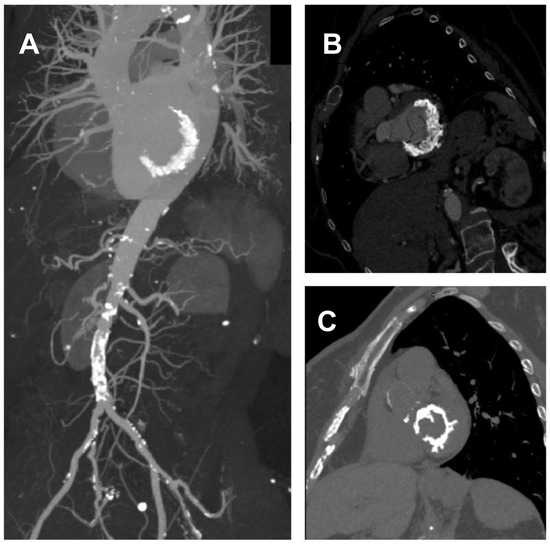

Figure 1. Severe MAC. (A,B): Heavily calcified annulus with a calcium thickness > 10 mm. (C): Calcium infiltration of the left ventricular free wall.

The protocol included preoperative CT scan to assess and stratify the severity of the MAC in all patients. Imaging analysis was performed by two experienced radiologists. The DICOM “OsiriX MD” viewer was used for post-processing, whereby a short-axis view of the MV annulus was obtained by means of multiplanar reformatting (MPR). Mitral annular analysis was carried out through angio-CT scan with or without cardiac gating, or through basal CT scan (Figure 1). MAC severity was categorized as mild, moderate or severe according to calcium thickness, calcium distribution, and trigone and leaflet involvement using a MAC CT-score ranging from a minimum of 1 to a maximum of 10 (Figure 2). Each category was further divided into three subgroups of severity. Briefly, the MAC was considered mild with a score from 1 to 3 points, moderate from 4 to 6 and severe when the score reached or exceeded 7 points [6]. From a surgical standpoint the annular extension of the MAC is a crucial issue, with extreme circumferential 360° lesions being the most difficult to approach.